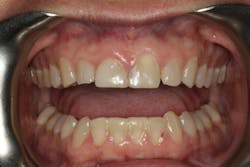

Phase 3: Equilibration and provisional restorations

We allowed the soft tissue to heal for four months following crown-lengthening surgery. We then refined our occlusion utilizing reductive equilibration. Following equilibration, we prepared teeth Nos. 5–12 and placed the patient in temporary restorations (figures 15 and 16). We use the temporary restorations to evaluate esthetics, phonetics, and function to ensure that the restorations are placed in functional harmony. Any refinements are completed in the provisional restorations, so the laboratory can use those as the blueprint for the final restorations.